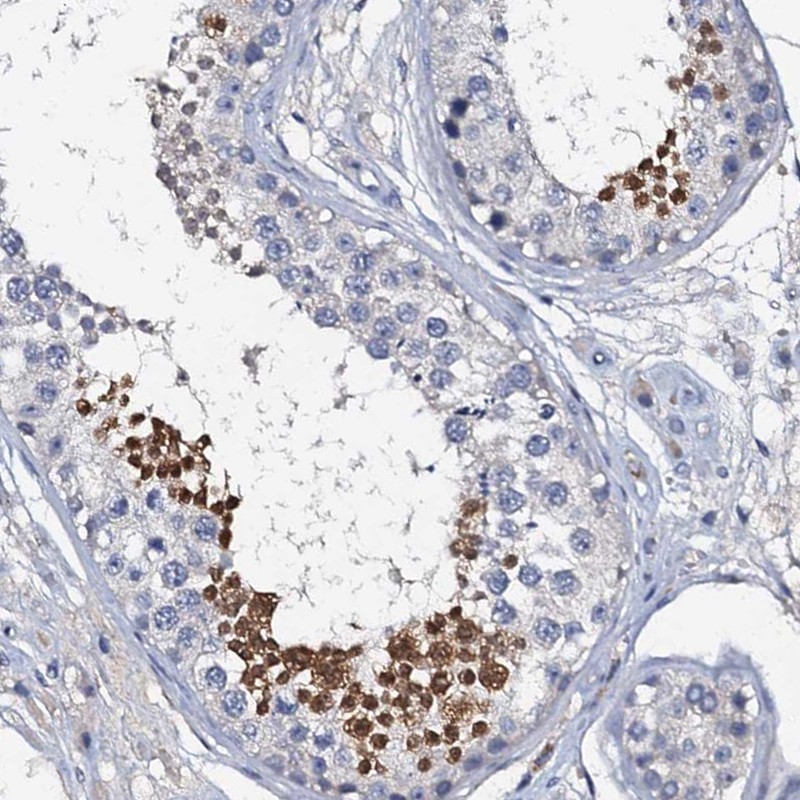

Immunohistochemistry analysis in human testis and stomach tissues using Anti-OLAH antibody. Corresponding OLAH RNA-seq data are presented for the same tissues.